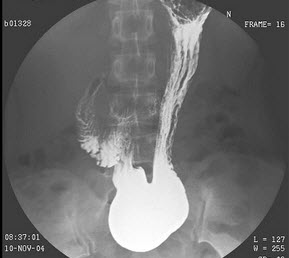

54、单项选择题

男,两月。表现排便困难、便秘、腹胀,经常哭闹。如图所示,最可能的诊断为()